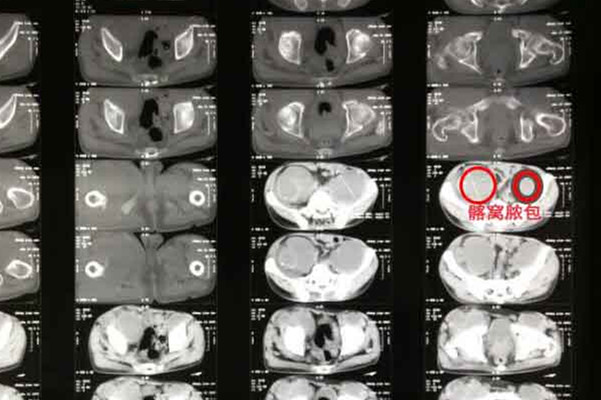

根据患者既往病史、结核接触史以及全身和局部症状进行诊断,因病程缓慢,应注意早期确诊;影像检查:早期X光照片可无明显改变,以后有骨质疏松,关节间隙变窄,以及骨质破坏和寒性脓肿;实验室检查:红血球沉降率多增速。在儿童有可疑时可作结核菌素试验,有关节积液时可作穿刺化验,查结核菌:病理组织检查,采取病理组织标本,在滑膜上取肉芽组织,骨骼上在X线片显示囊样病灶处取活体组织,其阳性率高。